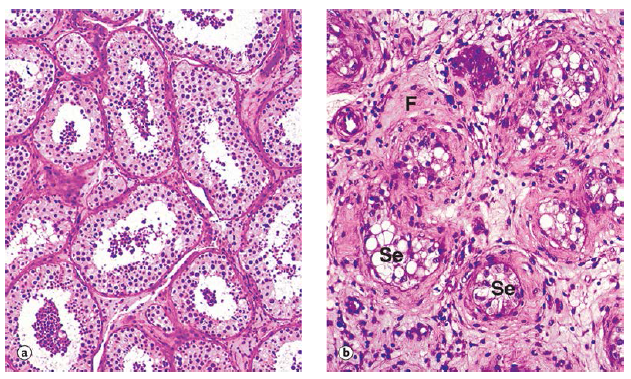

Q

describe the image

A

hyperplasia of mammary glands

a. inactive mammary gland

b. active mammary gland